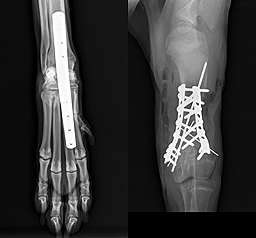

Beispiele aus der Orthopädie

- Frakturoperationen

- minimalinvasive Osteosynthese (MIPO, Fixateur externe etc.)

- Arthrodesen (Gelenksversteifung)

- Achsenkorrekturen von Gliedmaßenfehlstellungen